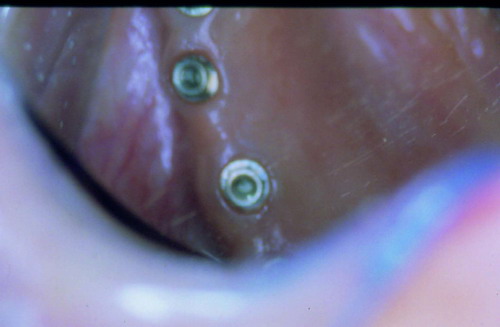

LA OCLUSIÓN MUTUAMENTE PROTEGIDA ES UN VIEJO CONCEPTO QUE CONSISTE EN LA MUTUA INTERACCIÓN DE LOS DISTINTOS GRUPOS DENTARIOS ENTRE SI. DE ESTA FORMA, LA TABLA PREMOLAR / MOLAR DE AMBOS HEMIMAXILARES ANTAGONISTAS, DETIENEN EL CIERRE MANDIBULAR EN CÉNTRICA, LOS CANINOS DISCLUYEN LAS PIEZAS POSTERIORES DURANTE LAS TRANSTRUSIONES, Y EL GRUPO INCISIVO LO MISMO DURANTE LAS PROPULSIVAS. SIN EMBARGO, DICHO CONCEPTO ES LIMITADO A LAS PIEZAS DENTARIAS, SIN TENER EN CONSIDERACIÓN LA IMPORTANTE FUNCIÓN QUE RECAE SOBRE LA ATM Y EN EL SOPORTE DE PRESIONES DURANTE ESTA DINÁMICA. ES ASI QUE EN EL AÑO 1981, EL DR. ANIBAL ALONSO GENERA EN LA CIUDAD DE BUENOS AIRES UN CONCEPTO MAS AMPLIO QUE DENOMINÓ : OCLUSION MUTUAMENTE COMPARTIDA. REF I EN EL QUE AMPLÍA EL CONCEPTO ANTERIOR, HACIENDO PARTÍCIPE A LA ATM EN LA MISMA. CUANDO EXISTE CARENCIA DE PIEZAS DENTARIAS POSTERIORES, YA SEA DE UN SOLO LADO O DE AMBOS , EL CIERRE MANDIBULAR ES DETENIDO POR LAS PIEZAS RESTANTE, FORZANDO A LA ATM A SOPORTAR PRESIONES MUY SUPERIORES A AQUELLAS PARA LAS QUE ESTA PREPARADA. FIG1 FIG2 FIG3 LUEGO DEL ESTUDIO CLÍNICO DE RIGOR, DONDE SE EVALÚA RADIOGRÁFICA Y PERIODONTALMENTE, SE PROCEDE A TOMAR MODELOS DE ESTUDIO Y MONTAR EN ARTICULADOR SEMIAJUSTABLE, SOBRE EL CUAL SE REALIZA UN ENCERADO PROGRESIVO DE DIAGNÓSTICO, A PARTIR DEL CUAL SE CONFECCIONA UN JUEGO COMPLETO DE PROVISIONALES DE AMBAS ARCADAS , INCLUYENDO LAS PIEZAS FALTANTES. SE ABORDA EL CASO YA QUIRÚRGICAMENTE DONDE EN UNA PRIMERA ETAPA SE TALLAN PRIMARIAMENTE LAS PIEZAS DENTARIAS Y SE PROCEDE, EXODONCIANDO EL INCISIVO CENTRAL SUPERIOR DERECHO, A REALIZAR UNA ROG(REGENERACIÓN ÓSEA GUIADA), PARA INMEDIATAMENTE INSTALAR PARTE DE NUESTROS PROVISORIOS EN LA GUIA ANTERIOR. SE ADAPTAN A LOS SECTORES POSTERIORES LAS PRÓTESIS REMOVIBLES QUE PORTABA, Y SE ESPERAN CUATRO MESES, AL CABO DE LOS CUALES SE REALIZA UN ESTUDIO CON DENTASCAN, MEDIANTE EL USO DE UNA FÉRULA RADIOLÓGICA CON TUBOS METÁLICOS , QUE NOS SERVIRÁ TAMBIÉN DE GUÍA QUIRÚRGICA. PROCEDEMOS ENTONCES A LA IMPLANTACIÓN DE LOS SECTORES EDÉNTULOS MEDIANTE IMPLANTES ROSCADOS Y TÉCNICA SEMI SUMERGIDA. TRANSCURRIDAS OCHO SEMANAS OBSERVAMOS UNA CORRECTA SALUD PERIMPLANTARIA, Y REALIZAMOS LA INSTALACIÓN DE LOS ABUTTMENTS ALCANZAMOS ENTONCES EL PUNTO EXACTO DONDE DEBEREMOS COMENZAR A RECONTRUIR EN FORMA PERMANENTE. PAZ DEL SISTEMA: CENTRICIDADARTICULAR-PAZ MUSCULAR-ESTABILIDAD- -ACOPLAMIENTO. BASES FUNDAMENTALES DE LA OCLUSIÓN ORGÁNICA FIG41 FIG42 PROCEDEMOS NUEVAMENTE A TOMAR IMPRESIONES, EN ESTE CASO DEFINITIVAS , MONTAR NUEVAMENTE EN ARTICULADOR, Y CONSTRUIR LAS RESTAURACIONES PERIFÉRICAS TOTALES EN BASE A PORCELANA SOBRE ORO GALVANIZADO. REF. II SOBRE LAS MISMAS TERMINADAS Y YA EN BOCA, CHEQUEÁMOS TODOS LOS ELEMENTOS QUE CONSTITUYEN UNA REHABILITACIÓN ORAL INTEGRAL, DESDE LA SALUD ENDODONTICA DE PIEZAS TRATADAS O NO, LA SALUD PERIODONTAL, EL AJUSTE PERIFÉRICO DE LAS RESTAURACIONES, LA ESTABILIDAD EN LA ATM, Y LAS FUNCIONES OCLUSALES, CHEQUEOS ESTOS QUE SE REPETIRAN EN CADA UNO DE LOS CONTROLES POST OPERATORIOS. FIG46 FIG47 FIG48 FIG66 FIG67 REFERENCIAS: REF I: OCLUSIÓN Y DIAGNÓSTICO EN REHABILITACIÓN ORAL REF. II ELECTROFORMACIÓN EN ODONTOLOGÍA RESTAURADORA.